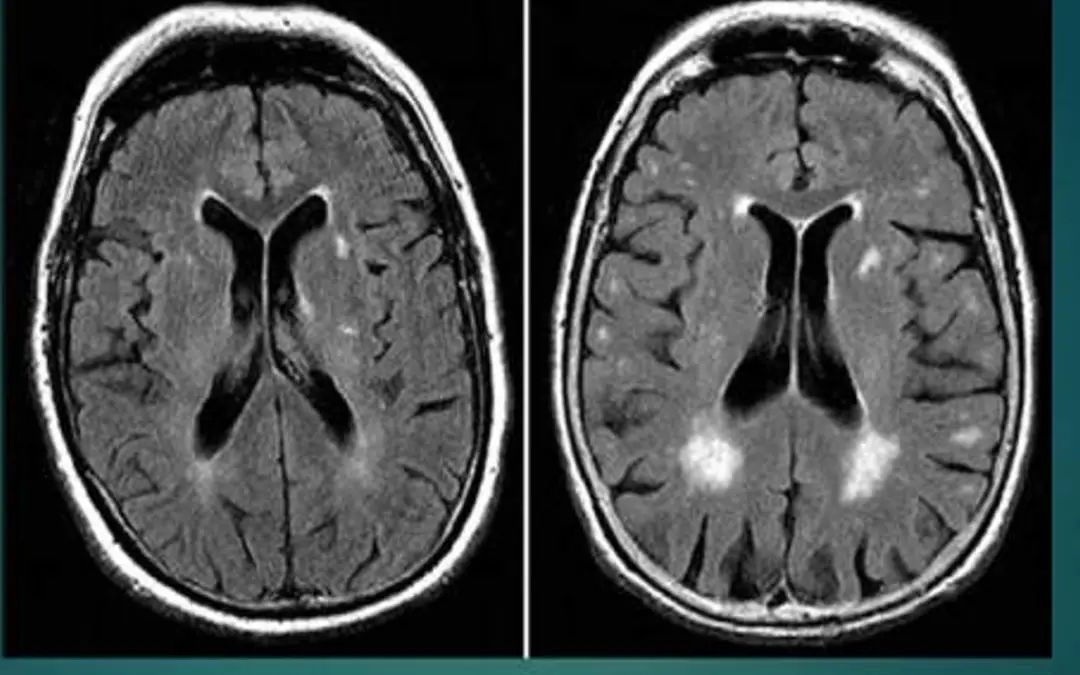

脑白质脱髓鞘

表现为皮层下白质及侧脑室周围多发点状或斑片状长Tl、长T2信号,可以与其他类型影像学损害并存。临床表现为精神障碍、行走困难、肌张力高、病理征阳性等。

此外,西班牙神经科学研究所,联合德国中央心理健康研究所的联合研究小组,将90名酗酒者的大脑磁共振成像,同36名不饮酒者进行对比分析,观察到了酗酒者大脑白质的持续退变过程。

酗酒者在清醒两周后(左)大脑中的电活动(蓝线)

明显少于禁酒者(右)

大脑扫描结果显示,酒精对两个大脑部位的影响最大,一个是海马体,另一个是前额皮质。记忆、情感、决策以及行为等均受这两个部位控制,因此上述功能会受到损伤。

与滴酒不沾相比,醒酒两周后,饮酒者大脑内神经元的电活动仍明显偏少,这种影响会在停止饮酒后持续6个星期。